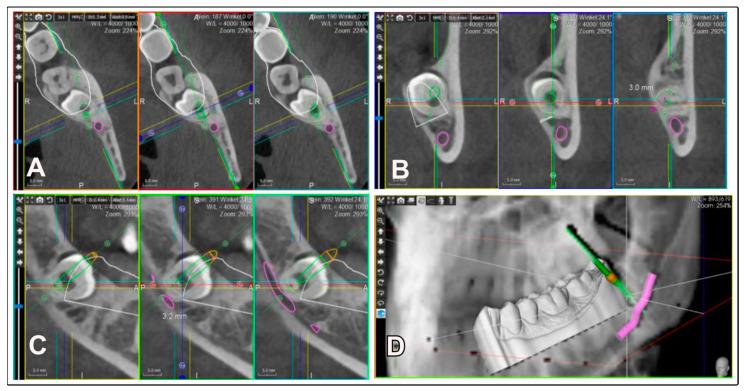

: The extraction of impacted mandibular third molars (M3Ms) carries significant risks, especially regarding the inferior alveolar nerve (IAN). This study aimed to evaluate the effectiveness of a 3D-planned inward fragmentation technique (3Dp-IFT) to improve surgical outcomes, reduce complications, and preserve bone structure in cases involving complex M3M impactions. : Twenty-three patients aged between 18 and 36 years requiring M3M removal were included. Preoperative planning involved the use of cone-beam computed tomography (CBCT) for precise localization of the furcation area, followed by the creation of a 3D navigation template using PlastyCAD software version 1.7. The surgical procedure was performed under local anesthesia, with meticulous endoscopic assistance to ensure accurate access and minimize trauma. Postoperative outcomes, such as bone loss, pain, swelling, and mouth opening range, were carefully measured. The data were systematically organized and analyzed descriptively using Microsoft Excel. : No disturbances to the IAN or lingual nerve were observed. The mean buccal bone loss was 2.2 mm, with a standard deviation of 1.2 mm. Postoperative pain and swelling were generally low, with significant reductions within the first week. The use of the 3D navigation template significantly improved surgical access, enhancing safety and minimizing complications. : The 3Dp-IFT technique represents a significant advancement in the minimally invasive removal of M3M by allowing precise access to critical anatomical areas while minimizing bone loss and postoperative complications. This approach is particularly beneficial for complex cases involving M3M near the IAN, thereby improving surgical safety and patient outcomes.

下颌阻生第三磨牙(M3M)的拔除存在重大风险,尤其是涉及下牙槽神经(IAN)时。本研究旨在评估三维规划向内劈开技术(3Dp-IFT)在改善手术效果、减少并发症以及在复杂M3M阻生病例中保留骨结构方面的有效性。23名年龄在18至36岁之间需要拔除M3M的患者被纳入研究。术前规划包括使用锥形束计算机断层扫描(CBCT)精确定位分叉区,随后使用PlastyCAD软件1.7版本创建三维导航模板。手术在局部麻醉下进行,在内镜的细致辅助下确保准确入路并将创伤降至最低。仔细测量术后结果,如骨丢失、疼痛、肿胀和开口度。使用Microsoft Excel对数据进行系统整理和描述性分析。未观察到IAN或舌神经受到干扰。颊侧骨丢失的平均值为2.2毫米,标准差为1.2毫米。术后疼痛和肿胀总体较轻,在第一周内有显著减轻。三维导航模板的使用显著改善了手术入路,提高了安全性并减少了并发症。3Dp-IFT技术通过允许精确进入关键解剖区域,同时将骨丢失和术后并发症降至最低,代表了M3M微创拔除的重大进展。这种方法对于IAN附近复杂M3M的病例特别有益,从而提高了手术安全性和患者预后。